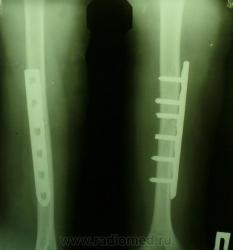

Какое, по Вашему мнению, качество фиксации отломков?

видится вполне нормальным..

По верхнему краю МТК небольшое расхождение с диафизом. Ось в норме. А в нижней трети диафиза б/б кости перелом ятрогенный?

б/б - это большеберцовая? Так на снимке вроде плечевая. И что такое МТК? Металическая конструкция? Все-таки многовато ОПРСТ в нашем лексиконеНедоволен...

Линия, пересекающая третий шуруп снизу и у нижнего края пластины - это артефакты, возникли после просмотров мокрой пленки травматологами. Ось плечевой кости восстановлена, а как насчет неплотного прилегания пластины?

Прошу прощения. Это плечевая кость. "Срезал" локтевой сустав в PAINTе.

Не б/б, а плечевая. Опечатка, sorry. МТК - металлоконструкция. У нас травматологи считают удовлетворительным, когда зазор между пластиной и костью не более 2-3 мм, и оси их (кости и пластины) совпадают, при остальных удовлетворительных условиях.

А я читал, что пластина должна плотно прилегать на всем протяжении, иначе возникает неравномерность давления на границах шуруп-кость, что-то типа зффекта рычага (если я внятно объяснил).

фиксация достойная плечевой кости, репозиция на 5, видно у докторов проблемма с шурупами, раз их скусывали, хорошая работа.

Переделывают, когда состояние отломков неудовлетворительное (боковое смещение в плечевой кости, к примеру, более половины диафиза, угловое более 170 градусов). В приведённом случае, как я считаю, вполне удовлетворительное состояние отломков после металлоостеосинтеза. Общие положения всегда рассматриваются относительно каждого конкретного случая.

ну повторная травма тут была точно т.к верхний шуруп вырван, больной лукавит, вот еще что разглядел в обл перелома проведен шуруп это не есть хорошо, будет препятствовать сращению, признаки консолидации есть, если дальше не раскачает, возможно срастется и так. вероятно рано сняли гипс

Именно!.. Травматологи - как никто другой - обязаны помнить об этом!! Поэтому и пластина должна плотно прилегать на протяжении, и бОльшая её часть должна находиться проксимальнее,

и фиксацию нужно производить УДЕРЖИВАЮЩИМИ шурупами (а не проходящими, как указал КАВ, ч/з место перелома)!!!

Вот именно! Если присмотреться, вокруг двух верхних шурупов имеются зоны остеолиза, особенно вокруг верхнего. Почему он возник? Я считаю, что из-за повышенного давления шурупа на кость. А насчет повторной травмы - конечно, пытать пациента никто не будет, но и без нее есть причины для возникновения несостоятельности пластины.

В данном случае через 2 месяца определяется миграция металлоконструкции, угловая деформация оси плеча. Не исключается повторный перелом. Возможно, несоблюдение режима пациентом. Как бы то ни было, налицо факт неудовлетворительного состояния отломков+миграция. В свою защиту могу только одно сказать: первично удовлетворительное состояние отломков не гарантирует нормальной консолидации.

Использована пластина LCP, в ней винты вкручиваются не только в кость, а еще есть резьба для фиксации головок винтов к самой пластине. Поэтому зазор между костью и пластиной шириной 2-4мм не влияет на прочность фиксации и даже приветствуется, так как считают, что меньше нарушается кровоснабжение в подлежащих мягких тканях. Другое дело, что несколько нарушены базовые принципы остеосинтеза. Дистально введены 3 винта, все прошли через оба кортикала, то есть дистальный фрагмент фиксирован к 6 кортикальным пластинкам. Это хорошо. Проксимально от перелома введены 2 винта, причем самый верхний прошел только через ближний к пластине кортикал (острый кончик винта не содержит резьбы - должен выходить на 2 мм из кости), то есть фрагмент удерживается только за три кортикальных пластины. Проксимально получается очень короткий рычаг.. Ну, еще третий винт введен через линию перелома, он ничего не фиксирует, плюс может замедлять консолидацию. По-моему, скусывали не только винты, а еще и проксимальный конец пластины. ИМХО, это основная причина несостоятельности - будь пластина на 1 отверстие больше проксимально и полноценно использовались винты - картинка была бы другой..